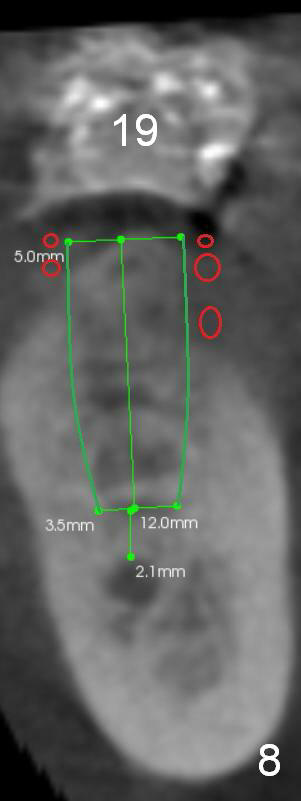

For the narrow ridge at the site of #19 (Fig.7), the coronal exposed threads of the 5x12 mm implant will be bone grafted (Fig.8 red circles).